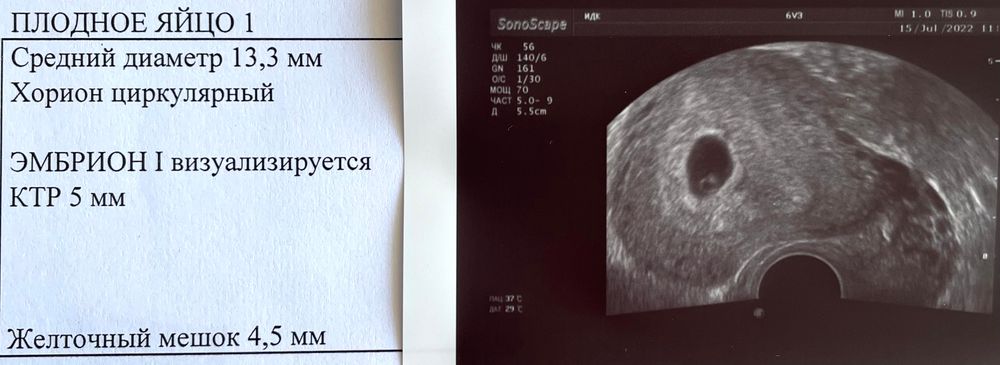

Изображение 6+2 с сердцебиением В 5+2 было только ПЯ

В 6 недель , было плодное яйцо. жду узи следующее для подтверждения сб :) будет уже 7,2 вообще после трех недель после задержки уже все видно :)

В 6.1 было только плодное яйцо. Эмбрион с сб увидели в 7.1